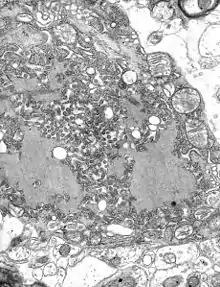

| MRI scan image shows high signal in the temporal lobes and right inferior frontal gyrus in someone with HSV encephalitis. | |